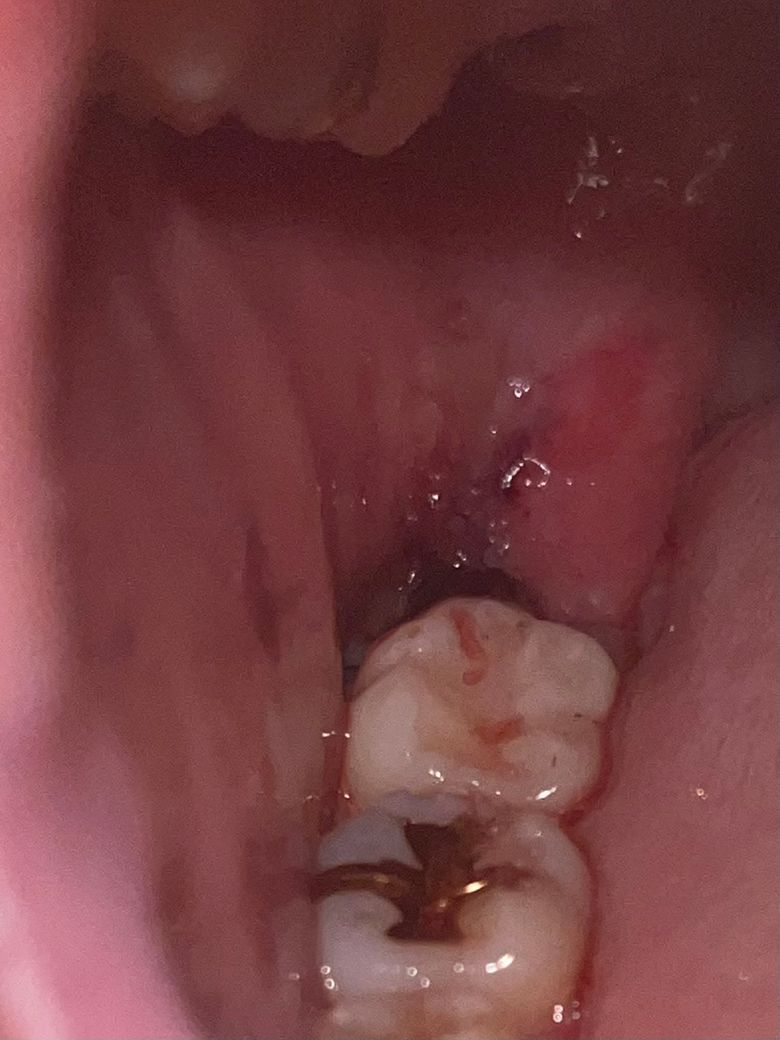

발치 이틀차에 발치 조직 주변이 하얗게 보여요

오늘 소독 다녀왔는데 잘 아물고 있다고 합니다 단순하게 뺀 거라서 아직까지 피떡 색도 그대로고 피랑 침 같이 섞여서 납니다 양치는 상관 없는지 그리고 조직도 괜찮은지 모르겠습니다ㅠㅠ

저정도면 정상적으로 아물고 있는 것이며 하얗게 보이는 것은 발치한 부위 주위 잇몸이 딱지 앉은 것이라 생각하면 됩니다. 피가 조금씩 스며나와 침과 섞일 수도 있지만 양은 많지 않습니다.

약간의 염증, 수포가 있긴 한데 치유와는 크게 상관없을 것 같습니다. 해당 부위 양치 살살해주시거나 주사기로 물 조심스럽게 쏴서 음식물 제거해주시기 바랍니다.